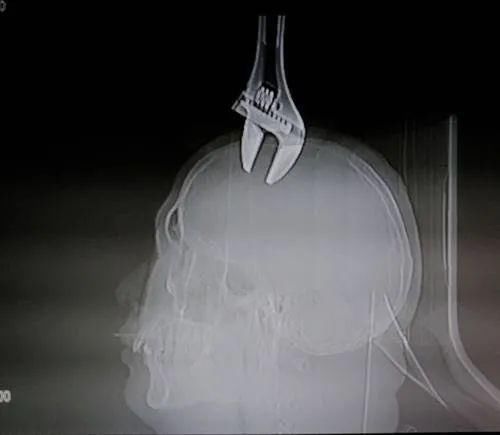

拍片显示

这个15厘米长的扳手

插入男子的头部2厘米

据医生介绍,扳手掉下来时候

不仅砸穿男子的颅骨、砸破了硬膜

而且扳手的尖部已经扎入了脑袋里面

伤者身体比较强壮,颅骨比较厚

扳手并没有扎得特别深